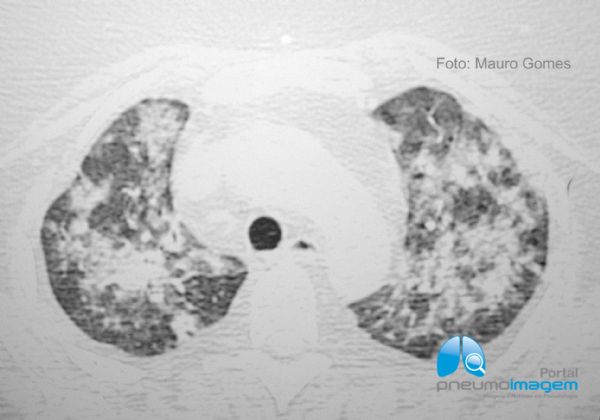

A pneumonia por CMV em pacientes imunocomprometidos não-AIDS aparece na TCAR como áreas mistas bilaterais de opacidade em vidro fosco, pequenos nódulos centrolobulares mal definidos e consolidação confluente especialmente nos lobos inferiores, como no caso em questão. O espessamento dos septos interlobulares e o derrame pleural podem estar associados. As imagens são de uma paciente imunodeprimida de 46 anos, pós-TMO.

CMV pneumonia in immunocompromised non-AIDS patients appears in HRCT as bilateral mixed areas of ground-glass opacity, poorly defined centrilobular nodules, and confluent consolidation, especially in the lower lobes, as in the case in question. Thickening of the interlobular septa and pleural effusion may be associated. The images are from a 46-year-old immunosuppressed patient, post-BMT.